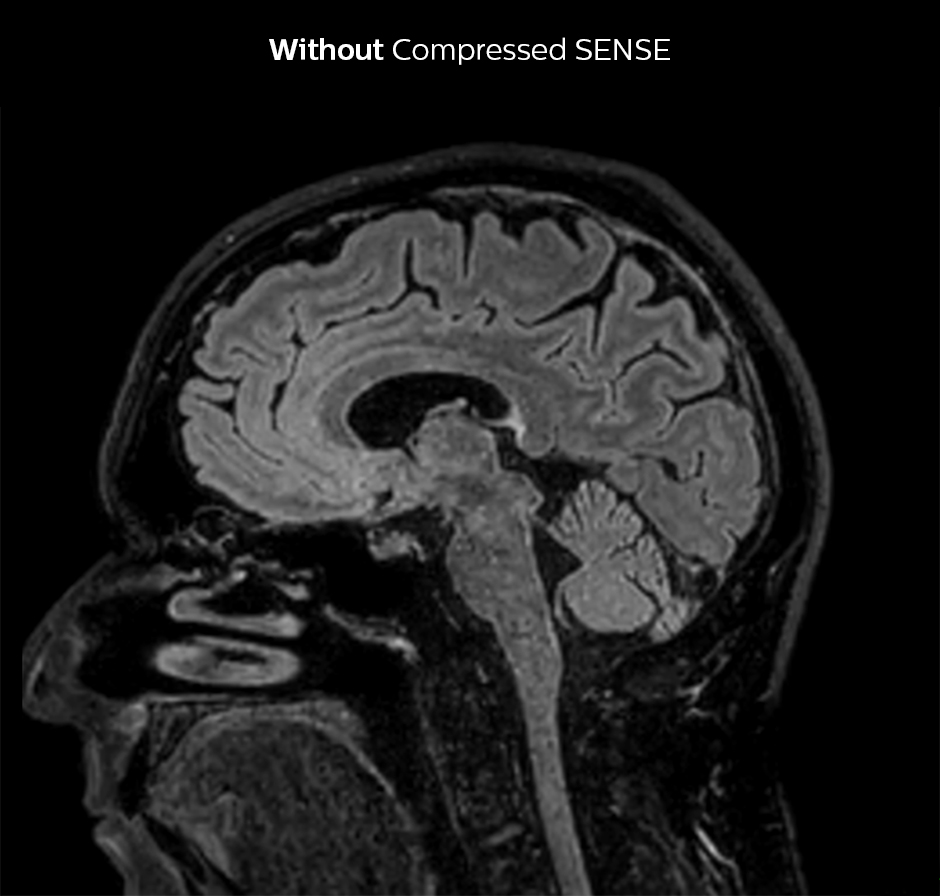

Shorter scan time in brain

Compressed SENSE allows 28% shorter scan time with the same spatial resolution.

3D FLAIR, scan time 5:02 min, voxel size 1.1 x 1.1 x 1.1 mm, Ingenia 1.5T.

3D FLAIR, scan time 3:36 min, voxel size 1.1 x 1.1 x 1.1 mm, Ingenia 1.5T.